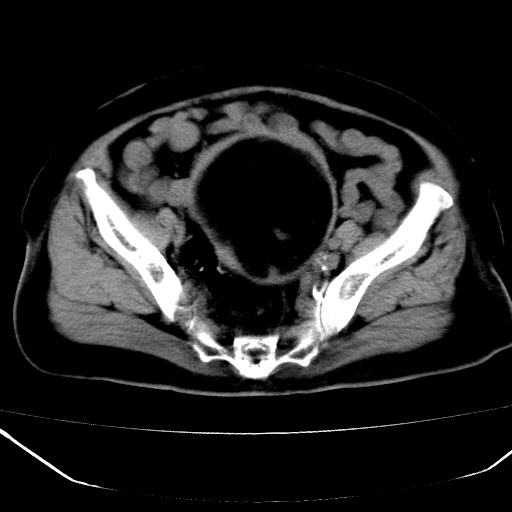

患者,女,74岁,无不适,b超示盆腔包块。

子宫前上方巨大脂性肿物,肿物边缘为较厚软组织密度影,其内缘欠光整,脂性密度中央见结节状软组织密度影“漂浮”,肿物与子宫前壁关系密切,考虑1脂肪瘤2皮样囊肿3肌瘤脂样变

ct值-90hu